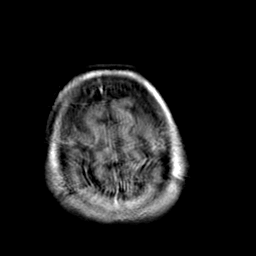

Creutzfeld-Jakob disease: gadolinium enchanced T1-Weighted MR -- Slice #21

[Home][Help][Clinical] Slice 21